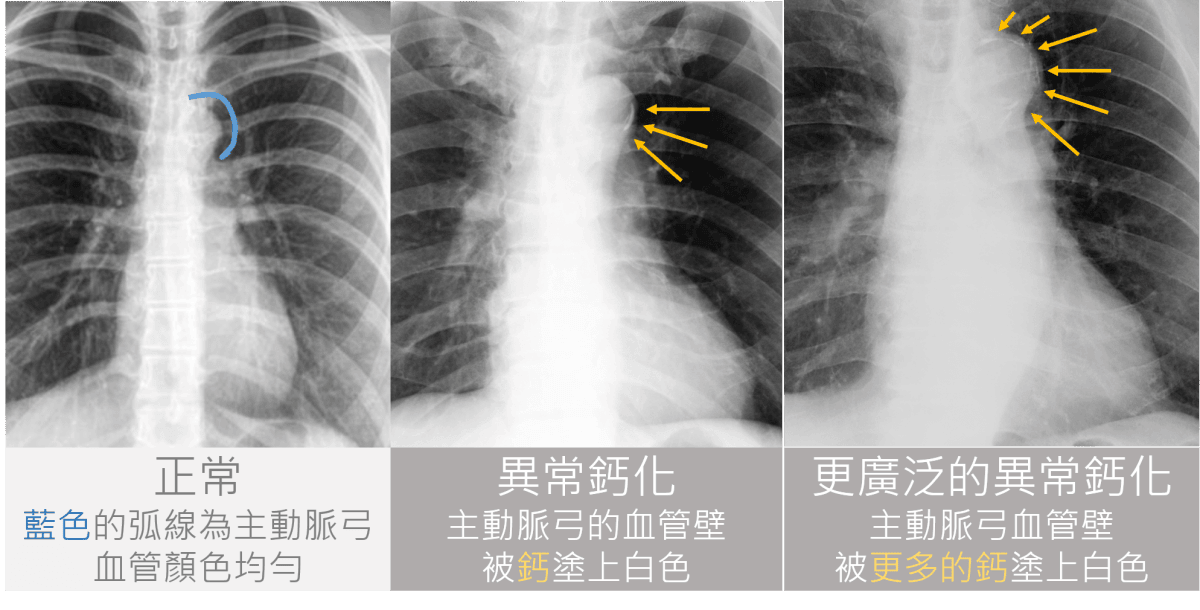

二、當腎友身體中的血管,有明顯鈣化的現象時,也要盡量限制鈣片的使用。

怎麼知道身體血管有鈣化呢?每年一次的胸部X光可以看主動脈弓是否鈣化。

aortic arch calcification

腹部側面照的X光,能夠評估腹主動脈的鈣化情況。

abdomen calcification